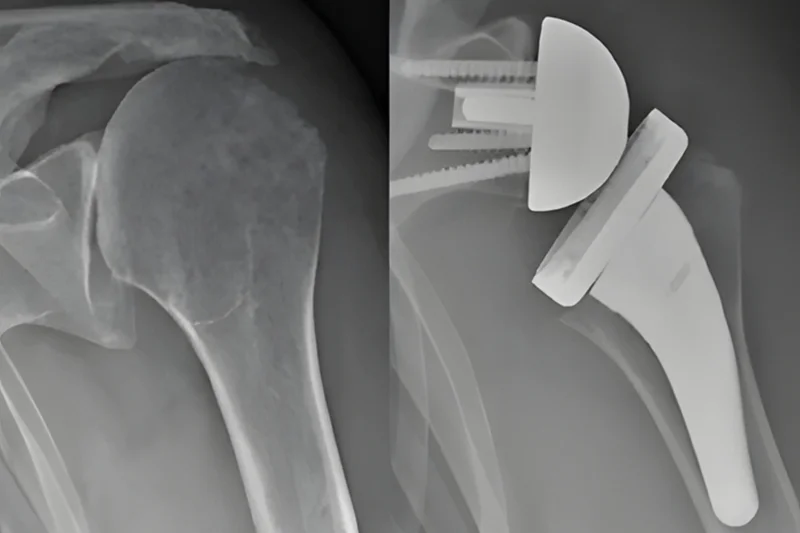

Shoulder replacement or arthroplasty is a surgical procedure recommended for patients suffering from severe shoulder conditions, such as advanced osteoarthritis or irreversible joint damage. The procedure involves replacing the damaged joint with a prosthesis specially designed to restore mobility and eliminate pain.

A shoulder prosthesis is a medical device used to replace a damaged shoulder joint, either partially or completely, with artificial metal and plastic components.

- Anatomical prosthesis: replaces both the humeral head and the glenoid cavity, and is recommended for patients with intact joints;

- Reverse prosthesis: suitable for patients with severe rotator cuff injuries, changing the position of the components to improve stability;

- Hemiarthroplasty: replaces only the humeral head and is used in certain fractures or partial damage to the joint.